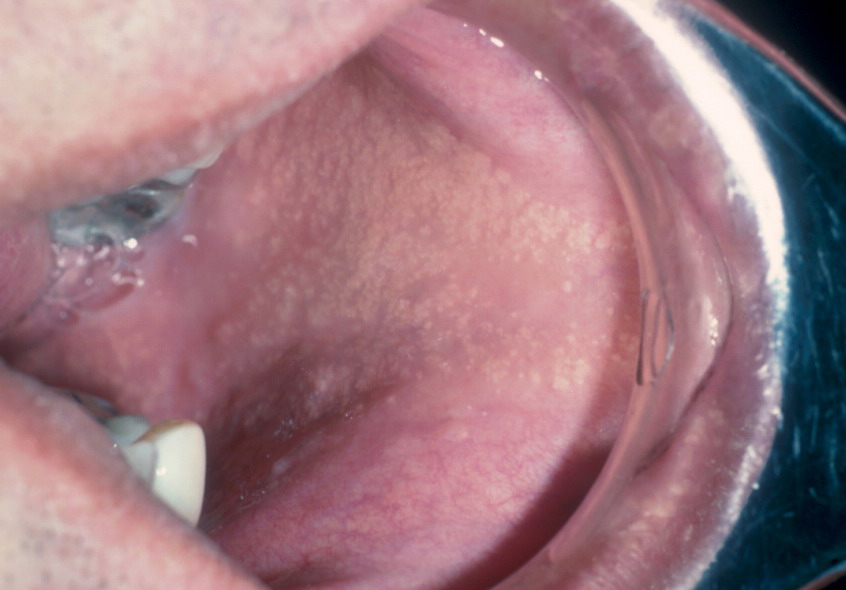

Fordyce spots

Fordyce spots are normal large, superficial sebaceous (oil-producing) glands seen on the moist tissue that lines some organs and body cavities (mucosal surfaces). The “spots” are asymptomatic and can be found on the head of the penis, the inner foreskin, and, most commonly, at the border of the lips. These sebaceous glands are not associated with hair follicles. These lesions are asymptomatic, but itching or irritation may occur if people treat the bumps inappropriately.